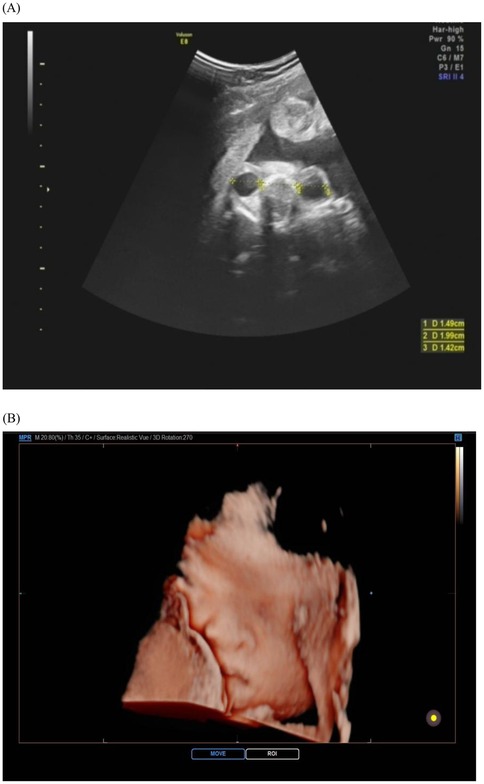

Bicoronal suture fusion constitutes the pathognomonic cranial hallmark of Apert syndrome, detectable sonographically from 18 gestational weeks. The most recognized manifestation is turribrachycephaly, characterized by a cranial index exceeding 90% (specificity 94%) and an abnormal fronto-occipital to biparietal diameter ratio >0.72, resulting in a towering cranial vault with frontal bossing (14). Crucially, modern ultrasound protocols now prioritize sutural biomarker analysis over isolated morphology assessment. Absence of the normal hypoechoic suture line, coupled with aberrant Doppler flow signals at coronal sutures, provides direct evidence of synostosis, reducing false positives from positional molding (10) (Figure 1).

Ultrasound images of the fetal skull in Apert syndrome. (A) Cross-sectional view showing fusion of the coronal suture, which is not visible due to synostosis. (B) Midsagittal view demonstrating an abnormal skull shape with a protruding forehead.

Figure 1. Ultrasound image of fetal skull in Apert syndrome: closed coronal suture (cross-section) and frontal bossing. (A) Cross-section view: the coronal suture, as seen in the cross-section of the skull, is closed and therefore not visible; (B) midsagittal view: the skull shape is abnormal, with a protruding forehead.